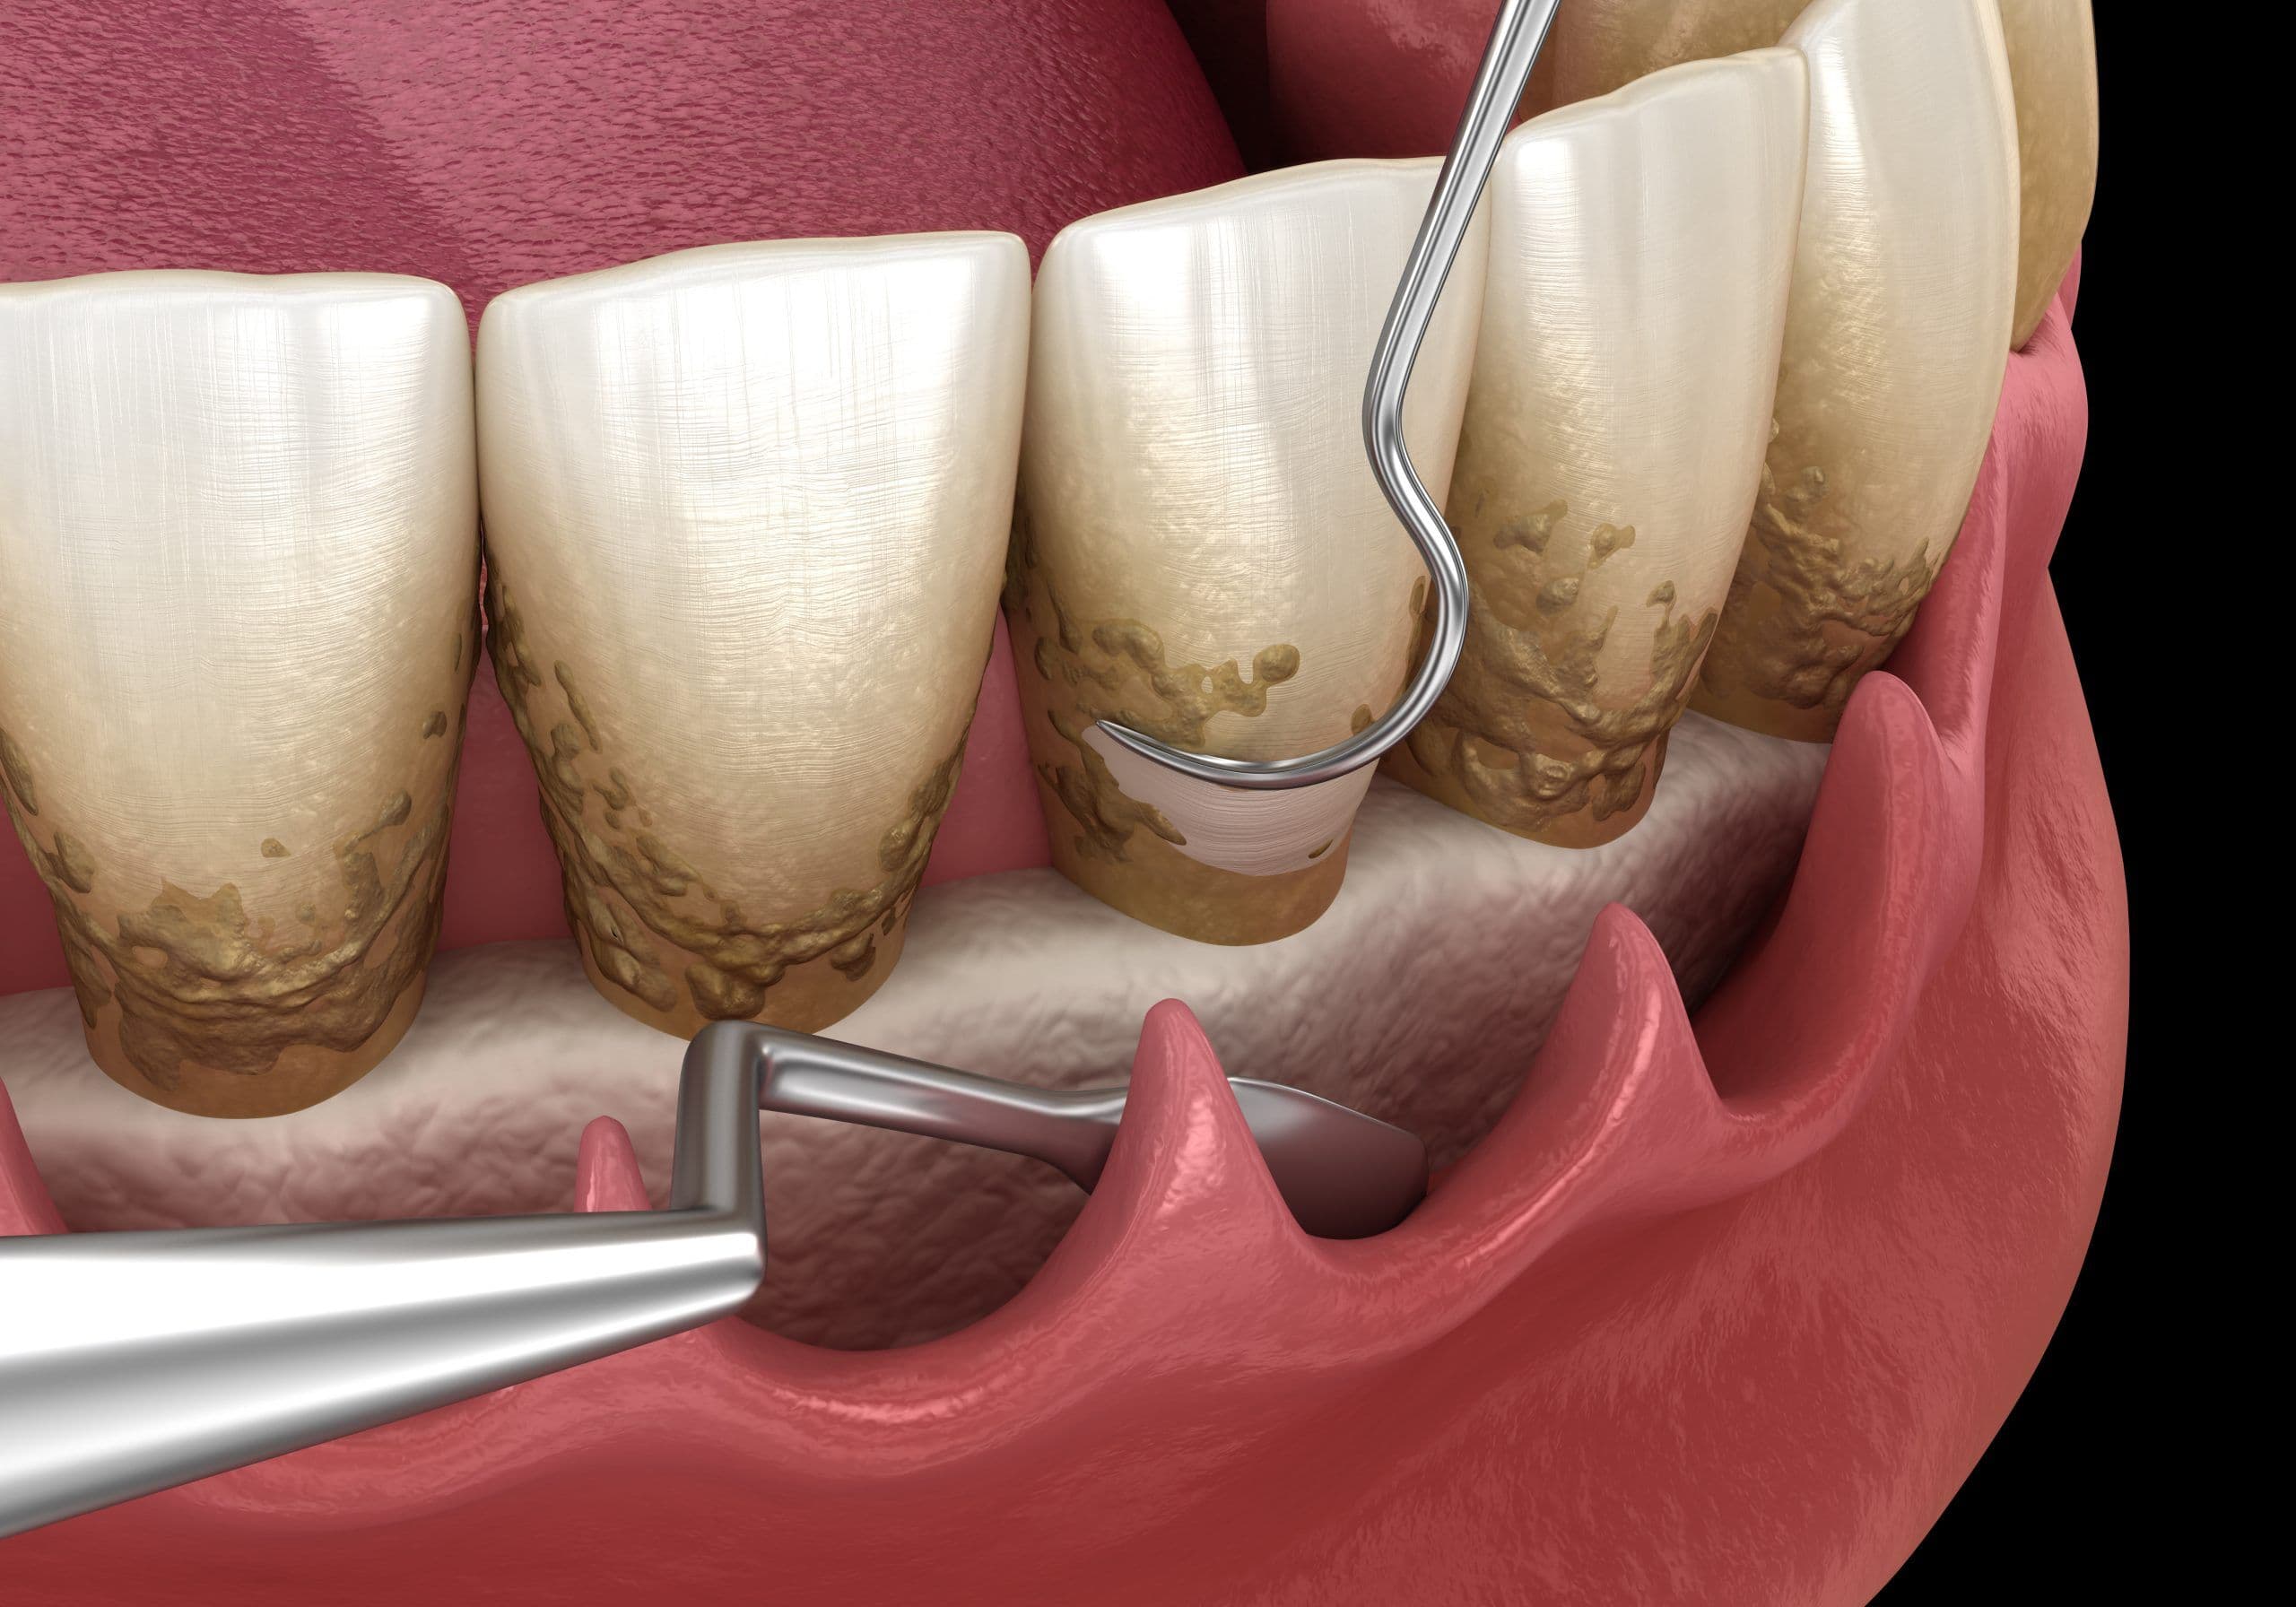

Структура зубов изнутри: фотографии и объяснения

Раздел: Фотомир